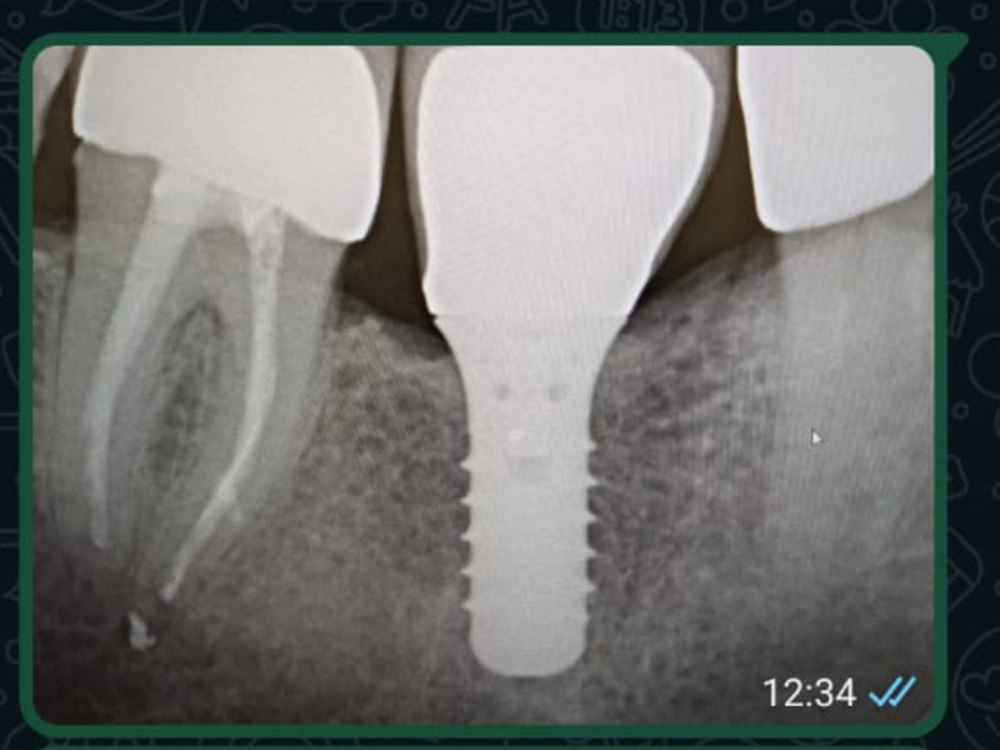

Dauerhafte und komfortable Alternative zu herkömmlichem Zahnersatz

Ob klassische Kronen und Brücken, moderne Implantatprothetik oder digitale Fertigung: Wir bieten Ihnen das komplette Spektrum der Zahntechnik – individuell, präzise und auf höchstem handwerklichen Niveau. Entdecken Sie unsere Leistungen im Detail.